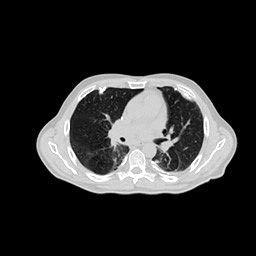

4.3 Few-View CT Reconstruction

In this section, the reconstruction performance of our proposed framework under few-view conditions will be tested. For the parallel-beam and fan-beam geometry, the number of views increases from to , uniformly distributing from to and to respectively. Such settings provide a complete benchmark of reconstruction performance, ranging from extremely sparse to relatively complete, full-view CT reconstruction. The experiment results are shown in Fig.5. Additionally, the ground truth, few-view ( views), and full-view ( views) CT reconstruction results of different methods are shown in the first and third rows of Fig.7 (parallel-beam, LIDC-IDRI dataset), and Fig.8 (fan-beam, LIDC-IDRI dataset).

4.4 Limited-Angle CT Reconstruction

To test the proposed framework’s performance on limited-angle reconstruction, we redo the experiment in the above section with the angular range changing from to for parallel-beam geometry and to for fan-beam geometry, one projection per degree. The experiment results are shown in Fig.6. Also, the ground truth and the limited-angle CT reconstruction results of different methods are shown in the row of Fig.7 (parallel-beam, LIDC-IDRI dataset), and Fig.8 (fan-beam, LIDC-IDRI dataset).

(a) Ground Truth

43.87dB

(b) ASD-POCS

47.96dB

(c) RBP-DIP

34.46dB

(d) DIP

26.63dB

(e) MED50

29.03dB

(f) RED-CNN

16.31dB